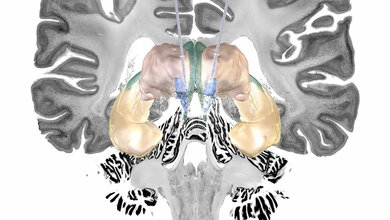

In genetischen Untersuchungen konnte gezeigt werden, dass der Patient eine neuartige, seltene Variante des Reelin-Gens in sich trägt. Reelin ist ein Protein, das eine zentrale Rolle bei der Regulierung der Entwicklung und Funktion von Hirnzellen spielt. Die Forschenden fanden in weiteren Studien unter Leitung des UKE heraus, dass diese Reelin-Genvariante vor der Zerstörung von Hirnzellen schützt, indem sie einem zentralen Entstehungsmechanismus bei Alzheimer entgegenwirkt – der Ablagerung des so genannten Tau-Proteins in Nervenzellen. Besonders stark war diese Schutzwirkung zudem im entorhinalen Kortex, einer Schlüsselregion des Gehirns für Lernprozesse und das Gedächtnis, deren Nervenzellen im Zuge einer Alzheimer-Erkrankung meist als Erstes geschädigt werden.

„Die schützende Genvariante, die in dieser Studie beschrieben wird, eröffnet eine neue Sichtweise auf das Reelin-Protein und die Entstehung von Alzheimer. Die Tatsache, dass ein Gen der Entwicklung der Alzheimer-Krankheit schützend entgegenwirkt, kann eine wichtige Grundlage für zukünftige Therapiestudien bilden“, sagt Dr. Diego Sepulveda-Falla vom Institut für Neuropathologie des UKE. Ihre Studienergebnisse haben die Wissenschaftlerinnen und Wissenschaftler im Fachjournal Nature Medicine veröffentlicht. 2019 war ein ähnlicher Erkrankungsfall aus derselben Population untersucht worden. Hier wurde eine genetische Variante in einem anderen Protein identifiziert, die für den verlangsamten Krankheitsverlauf verantwortlich war. Beide Fälle weisen gleichwohl auf einen ähnlichen Erkrankungsmechanismus im entorhinalen Kortex hin.